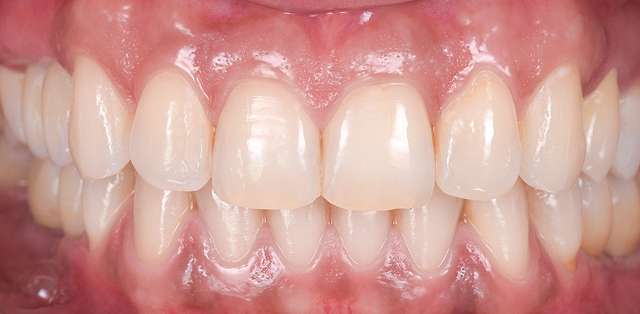

Pentru un rezultat estetic ideal, design-ul final trebuie sa fie intotdeauna referinta pentru chirurgie. Design-ul si computerul tomograf al pacientului sunt compilate pentru a primi pozitia ideala a implanturilor dentare